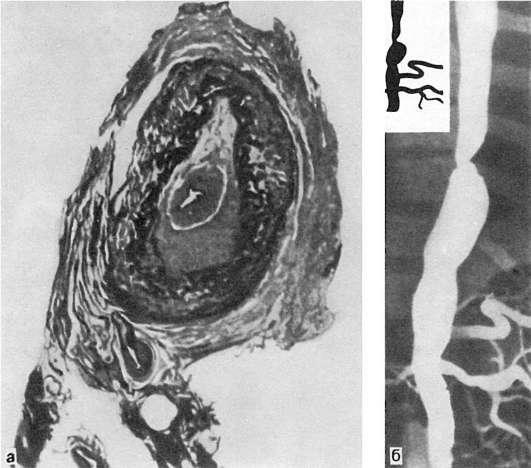

мелкого калибра. Сосуды имеют характерный вид: их стенки утолщены, ригидны, представлены белесоватой тканью. Интима может иметь утолщения, суживающие просвет, в котором обнаруживаются пристеночные или обтурирующие тромбы (рис. 165). В адвентиции и периваскулярной ткани выражены явления склероза, встречаются аневризматические выпячивания стенки. Поражение может быть сегментарным или диффузным. В зависимости от макроскопической картины различают стенозирующий,

Рис.

165. Неспецифический аортоартериит:

а - аорта; резкое утолщение стенки и окклюзия просвета; б - сужение нисходящей части грудной аорты, стеноз чревной и обеих почечных артерий, окклюзия верхней брыжеечной артерии (аортограмма, препарат А.В. Покровского)

ки. Интима утолщена за счет пролиферации эндотелия и пристеночных тромбов. Наибольшие изменения отмечаются в медии и адвентиции. В поздней (подострой) стадии описанные изменения сменяются продуктивной реакцией с формированием гранулем из макрофагов, эпителиоидных, гигантских и плазматических клеток, лимфоцитов. В финальной (склеротической) стадии развивается склероз стенки сосуда, в которой видны остатки внутренней эластической мембраны. Обнаруживаются организация тромботических масс, васкуляризация средней оболочки и стеноз просвета, вплоть до полной облитерации.